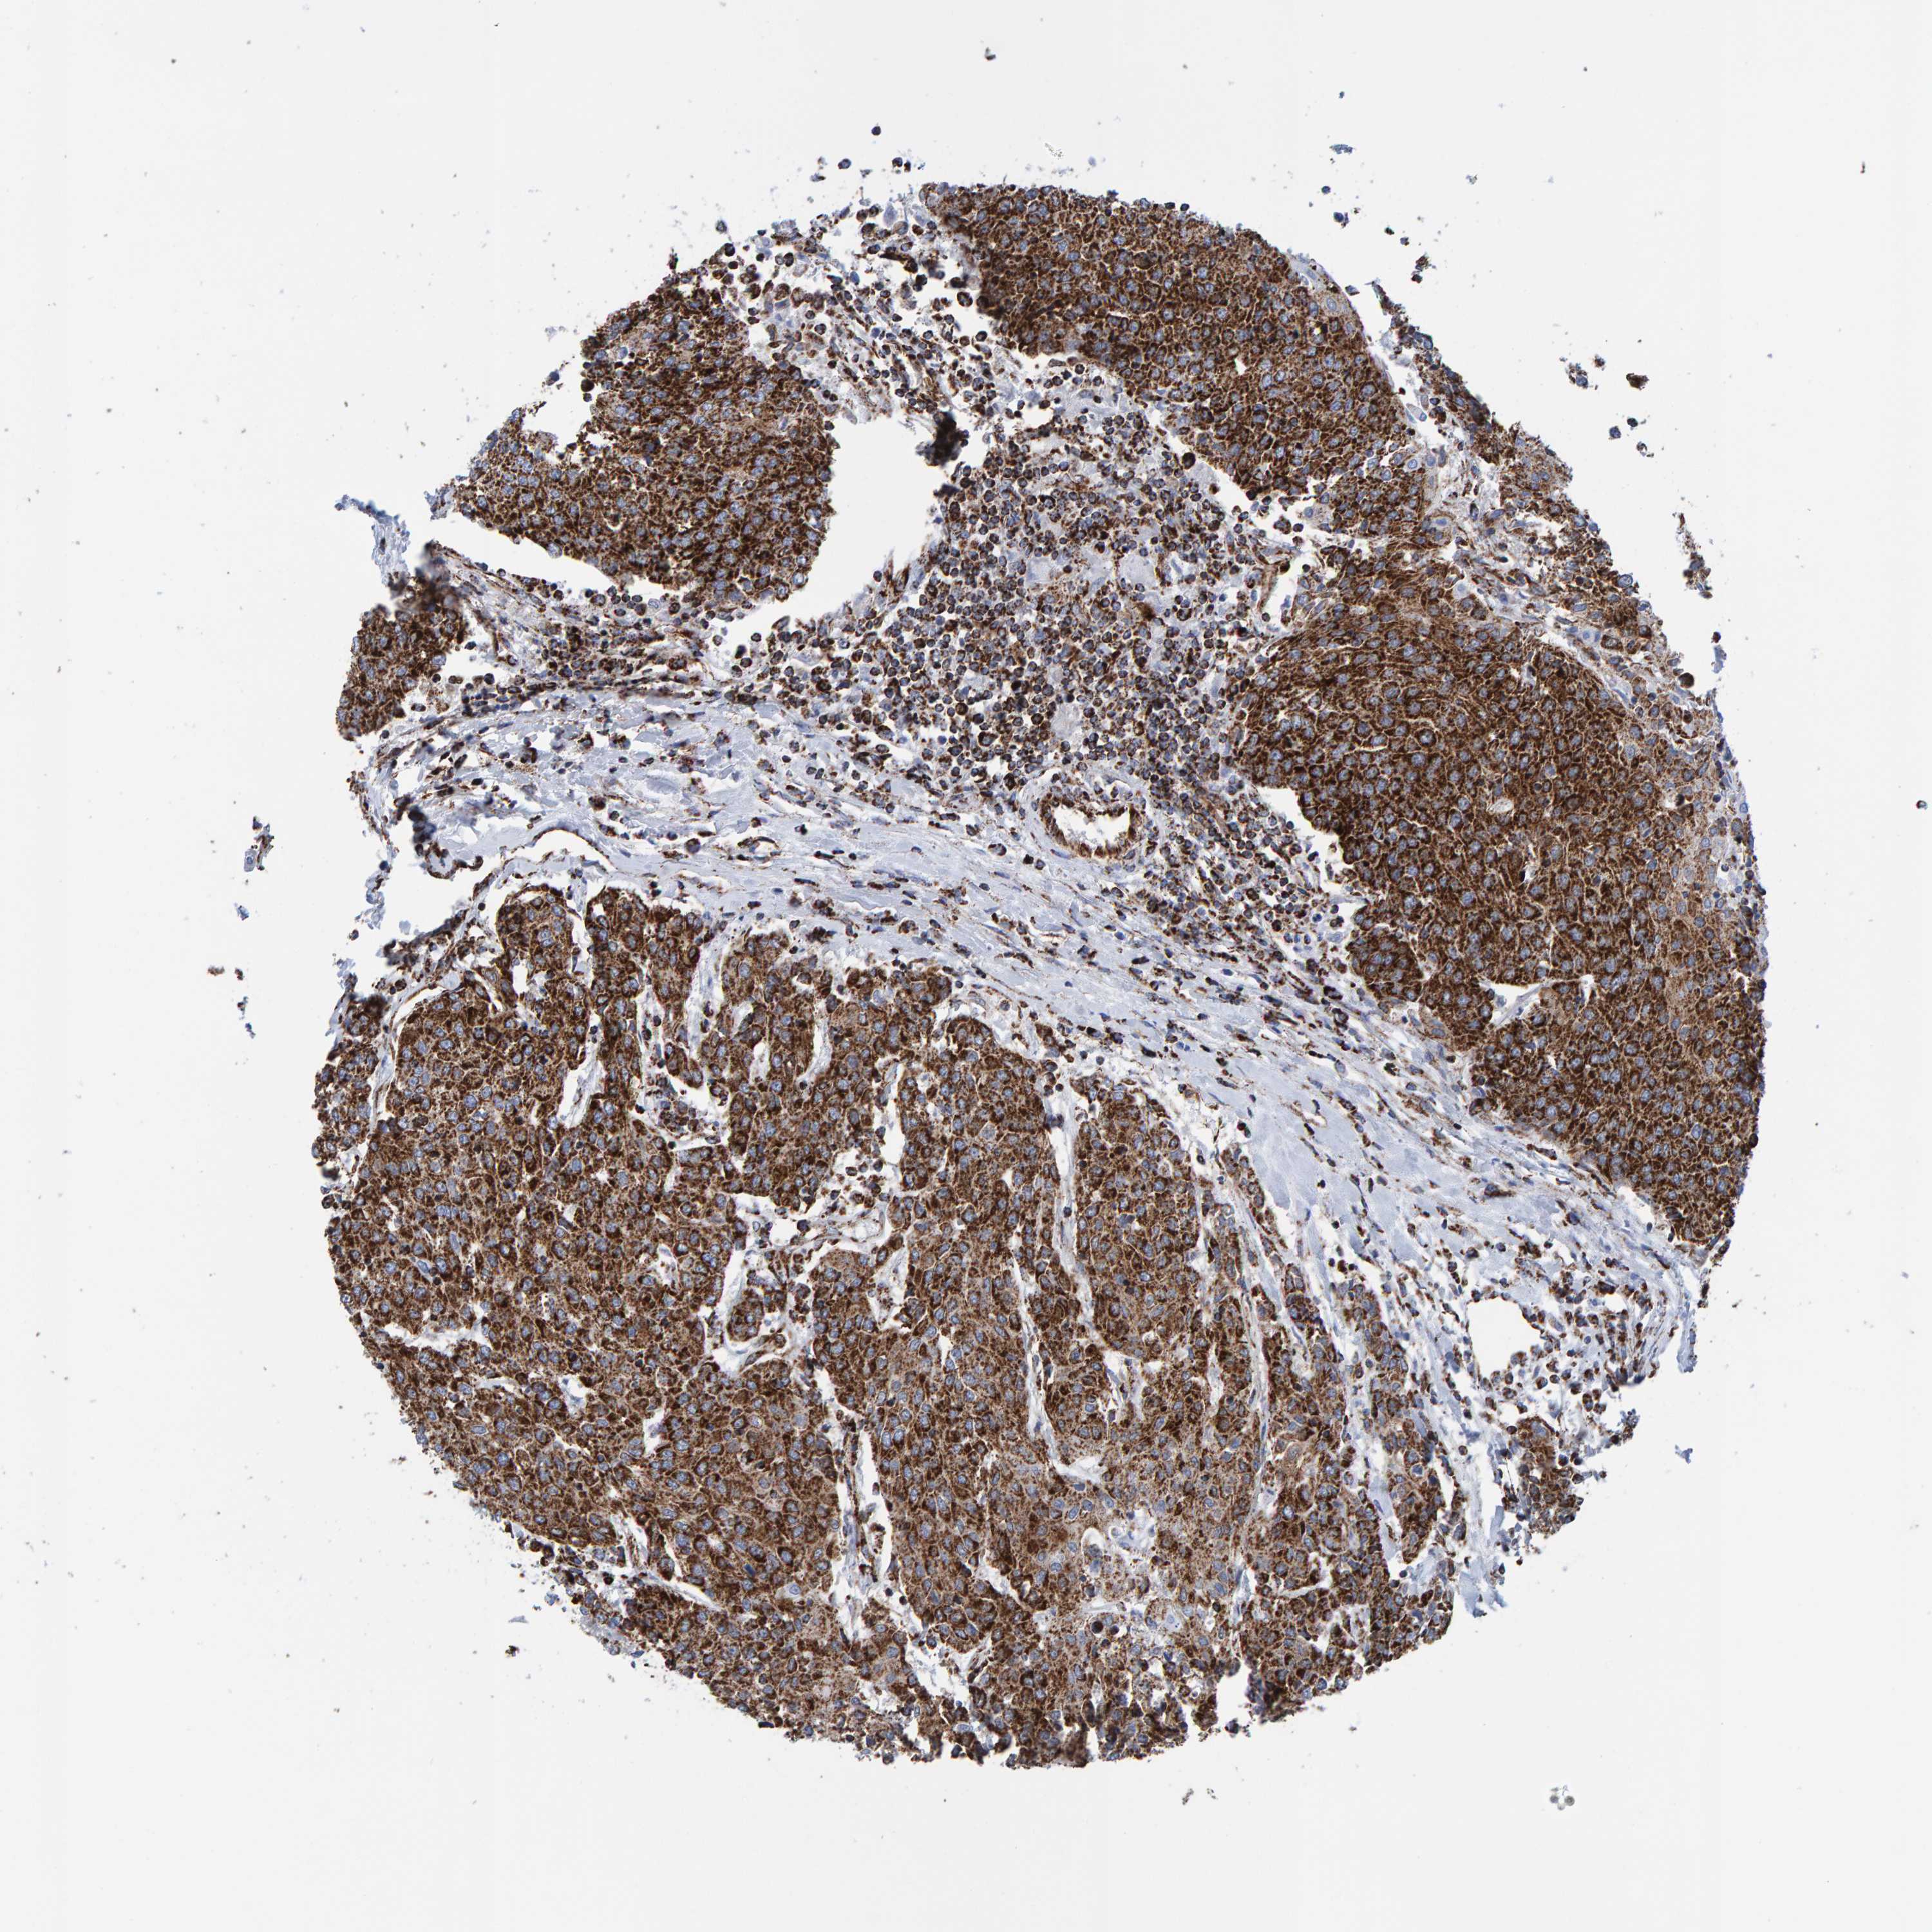

UROTHELIAL CANCER - Protein expressioni

A mouse-over function shows sample information and annotation data. Click on an image to view it in a full screen mode. Samples can be filtered based on level of antibody staining by selecting one or several of the following categories: high, medium, low and not detected. The assay and annotation is described here.

Note that samples used for immunohistochemistry by the Human Protein Atlas do not correspond to samples in the TCGA dataset.

Antibody stainingi

Antibody staining in the annotated cell types in the current human tissue is reported as not detected, low, medium, or high, based on conventional immunohistochemistry profiling in selected tissues. This score is based on the combination of the staining intensity and fraction of stained cells.

Each image is clickable and will lead to virtual microscopy that enables deeper exploration of all samples and also displays staining intensity scores, fraction scores and subcellular localization as well as patient and tissue information for each sample.

Antibody HPA022853

Antibody HPA023043

Antibody HPA023048

Staining

High

Medium

Low

Not detected

Intensity

Strong

Moderate

Weak

Negative

Quantity

>75%

75%-25%

<25%

None

Location

Nuclear

Cytoplasmic/membranous

Cytoplasmic/membranous,nuclear

Urothelial carcinoma, Low grade

Urothelial carcinoma, High grade